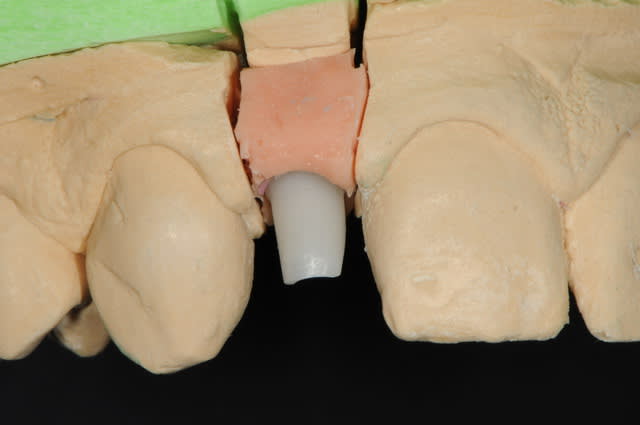

01/09/2010 à 16h28

-cicatrisation de la première vis de cica,

-diamètre plus gros pour la vis de cica

- pilier pour la provisoire

- provisoire moule ION

- ajustage

- polissage soigneux

la suite tout à l'heure, ça sonne à la porte...